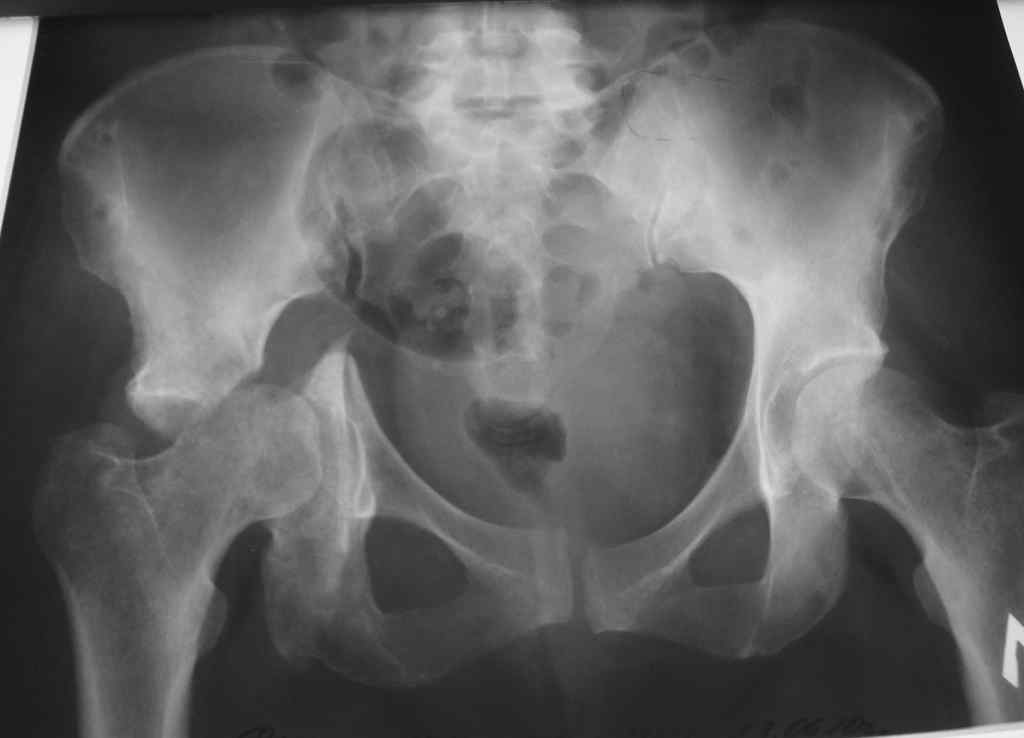

Доброе время суток уважаемые коллеги. На обсуждение выносится пациентка 42 лет. Травма 7 месяцев назад - ДТП. В одной из районных больниц выполнена фиксация таза и бедра в аппарате.

Через 4 мес. аппарат демонтирован. На контрольных рентгенограммах через 3 недели после демонтажа аппарата выяснилась данная рентгенкартина и пациентка направлена к нам в клинику с диагнозом ложный сустав дна вертлужной впадины.При визуальном осмотре пациентка находится на постельном режиме с момента травмы. Не активизирована.

Мнения о тактике лечения в отделении разошлись.То ли выполнить (насколько это возможно в такие сроки) открытую репозицию с костной аутопластикой и экстракортикальным остеоситнезом, то ли идти на первичное эндопротезирование ТБС с пластикой дна вертлужной впадины.

Хотелось бы посмотреть inlet. Похоже, что не репонирован разрыв правого КПС. Учитывая возраст и картинку - надо пытаться выполнить реконструкцию впадины, при чем начать с КПС.Поперечный перелом не срастется в таком положении никогда, т.е вам придется выполнить первично-ревизионное эндопротезирование. В 40 лет такой протез простоит недолго, т.е. вероятны 2-3 ревизии, если это будет выполнимо. от того, насколько удастся восстановить конгруэнтность сустава будет зависеть - сколько человек на этом суставе проходит, да и эндопротезированием можно будет обойтись стандартным. Если нет опыта реконструкции подобных повреждений - отправьте туда, где он есть.

Я бы провел реконструкцию и затем протез, если будут боли.Для разработки плана реконструкции нужно дообследование.Полипроекционная рентгенография, кт, состояние головки, движения, вес и т.д.